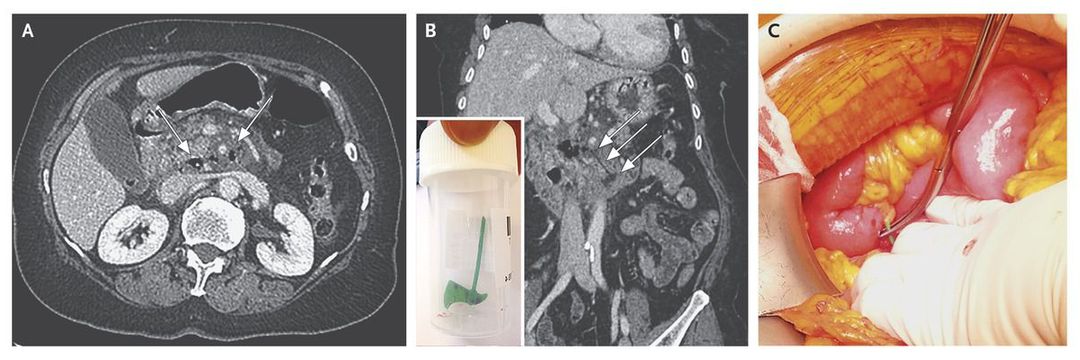

A 72-year-old woman presented to the emergency department with a 3-day history of periumbilical pain. She had had one episode of vomiting. She had no other notable medical history. Physical examination showed a temperature of 38°C and right abdominal tenderness without contracture. Laboratory tests showed a C-reactive protein level of 256 mg per liter and a white-cell count of 19,300 per cubic millimeter, with 90% neutrophils. A contrast-enhanced computed tomographic (CT) scan of the abdomen obtained during the portal venous phase shows infiltration of the root of the mesentery surrounding the superior mesenteric artery in association with pneumoretroperitoneum (Panel A, arrows). A CT reconstruction image in the coronal plane shows hypoattenuation of an ax-shaped foreign body perforating the third portion of the duodenum (Panel B, arrows). An exploratory laparotomy revealed the cause of the perforation (Panel C, green plastic gripped by the forceps), which was a plastic ax that was 2 cm long (Panel B inset). The patient reported that she had eaten a Christmas cake 7 days earlier. The perforation was repaired with sutures, and the patient recovered and was discharged after 10 days of hospitalization.